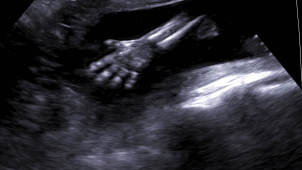

Už druhý rok za sebou je srpen nejplodnější měsíc v porodnici Nemocnice Šternberk. Mezi více než…